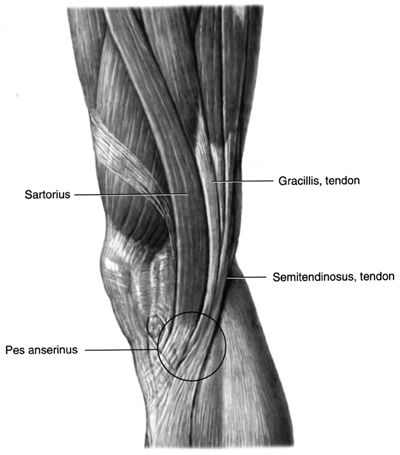

Foot

Perform all 3 views for trauma and nontrauma cases. A

limited 2-view foot is discouraged. Weight-bearing to assess foot

alignment. Non–weight-bearing if painful to stand or looking for a

foreign body or mass. Non–weight-bearing if ulcer and looking for

osteomyelitis. Always remove socks!

Consider US for Morton’s neuroma or plantar fasciitis, or

superficial mass. CT is good for full assessment of Lisfranc injuries.

MRI good for occult fracture or mass.

![]() |

|

Figure 20 (A) AP (dorsoplantar). (B) Medial oblique. (C) Lateral (mediolateral projection).